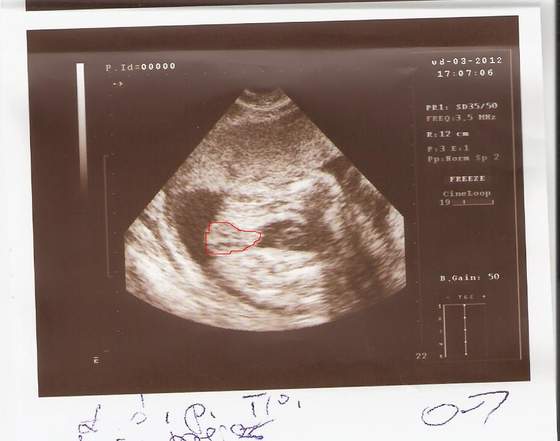

A tak prezentuje się aktualna kwatera naszej córci

Zobacz załącznik 445152Zobacz załącznik 445153